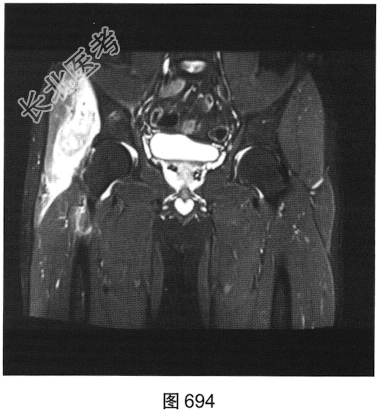

- 多项选择题2.[提示]患者行MRI平扫及增强扫描,见图692~图697。患者MRI平扫及增强扫描图像有哪些阳性表现( )

A、肿块边界不清,信号不均匀

B、肿块周围水肿明显

C、增强扫描肿块呈均匀强化

D、肿块边界清楚,信号均匀

E、增强扫描肿块及周围软组织呈明显不均匀强化

F、与邻近肌肉相比,T1WI呈等信号;T2压脂序列呈明显高信号